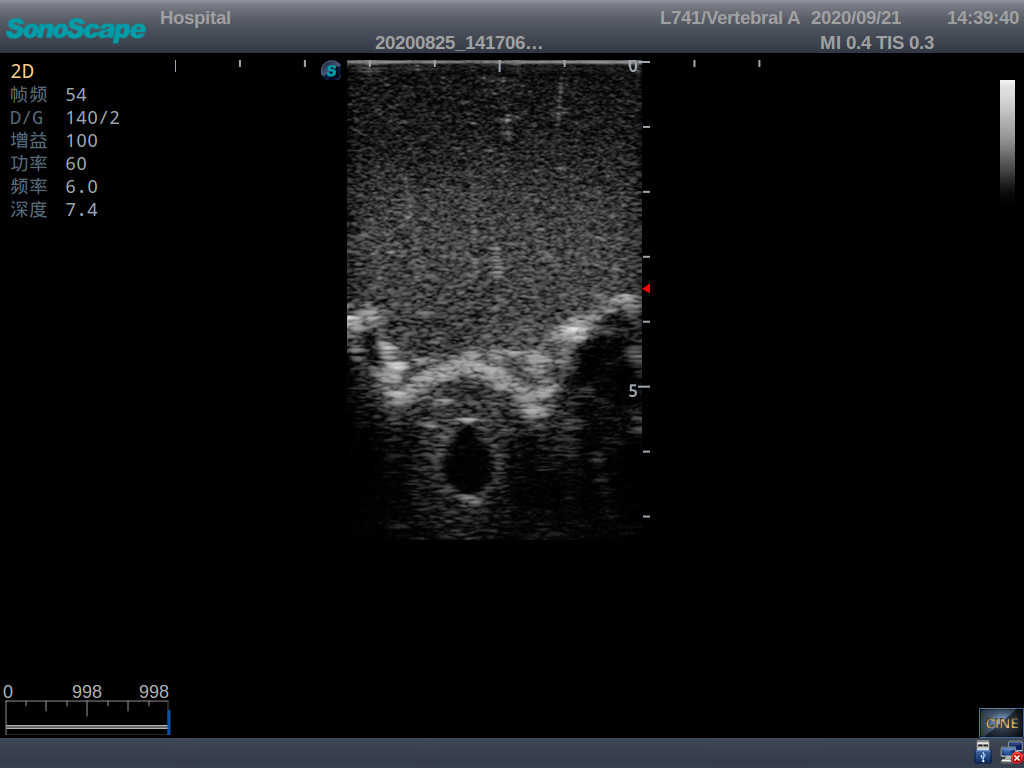

Model TYE1549.2

This model is an ideal choice for ultrasound-guided adult lumbar puncture training with true-to-life skin feel and touch, accurate anatomical structures as well as real clinical ultrasound images. Realistic resistance to needle tips and correct landmarks provide excellent hands-on experience.

2)  Real clinical ultrasound images